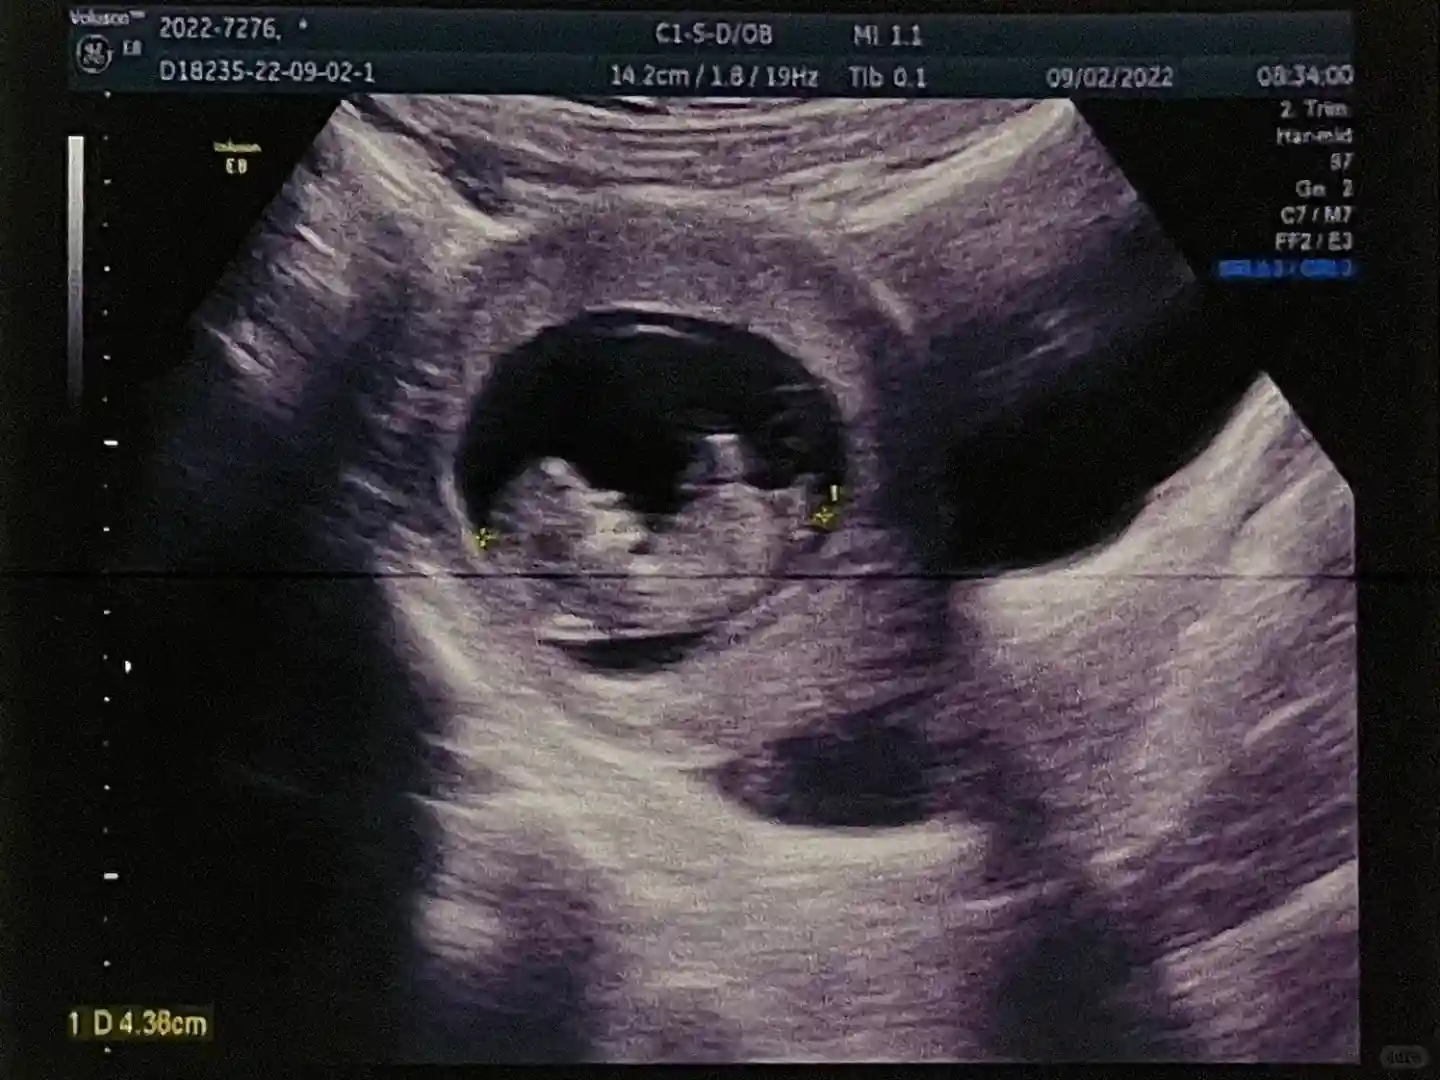

就这样我挺过了一超、二超、nt,中间经历了一次出血保胎又回到了小心翼翼的状态。看着我的小橙子有了胎心胎芽,B超单里逐渐有了形状,试管成功才有了真切的实感,我终于怀孕了!